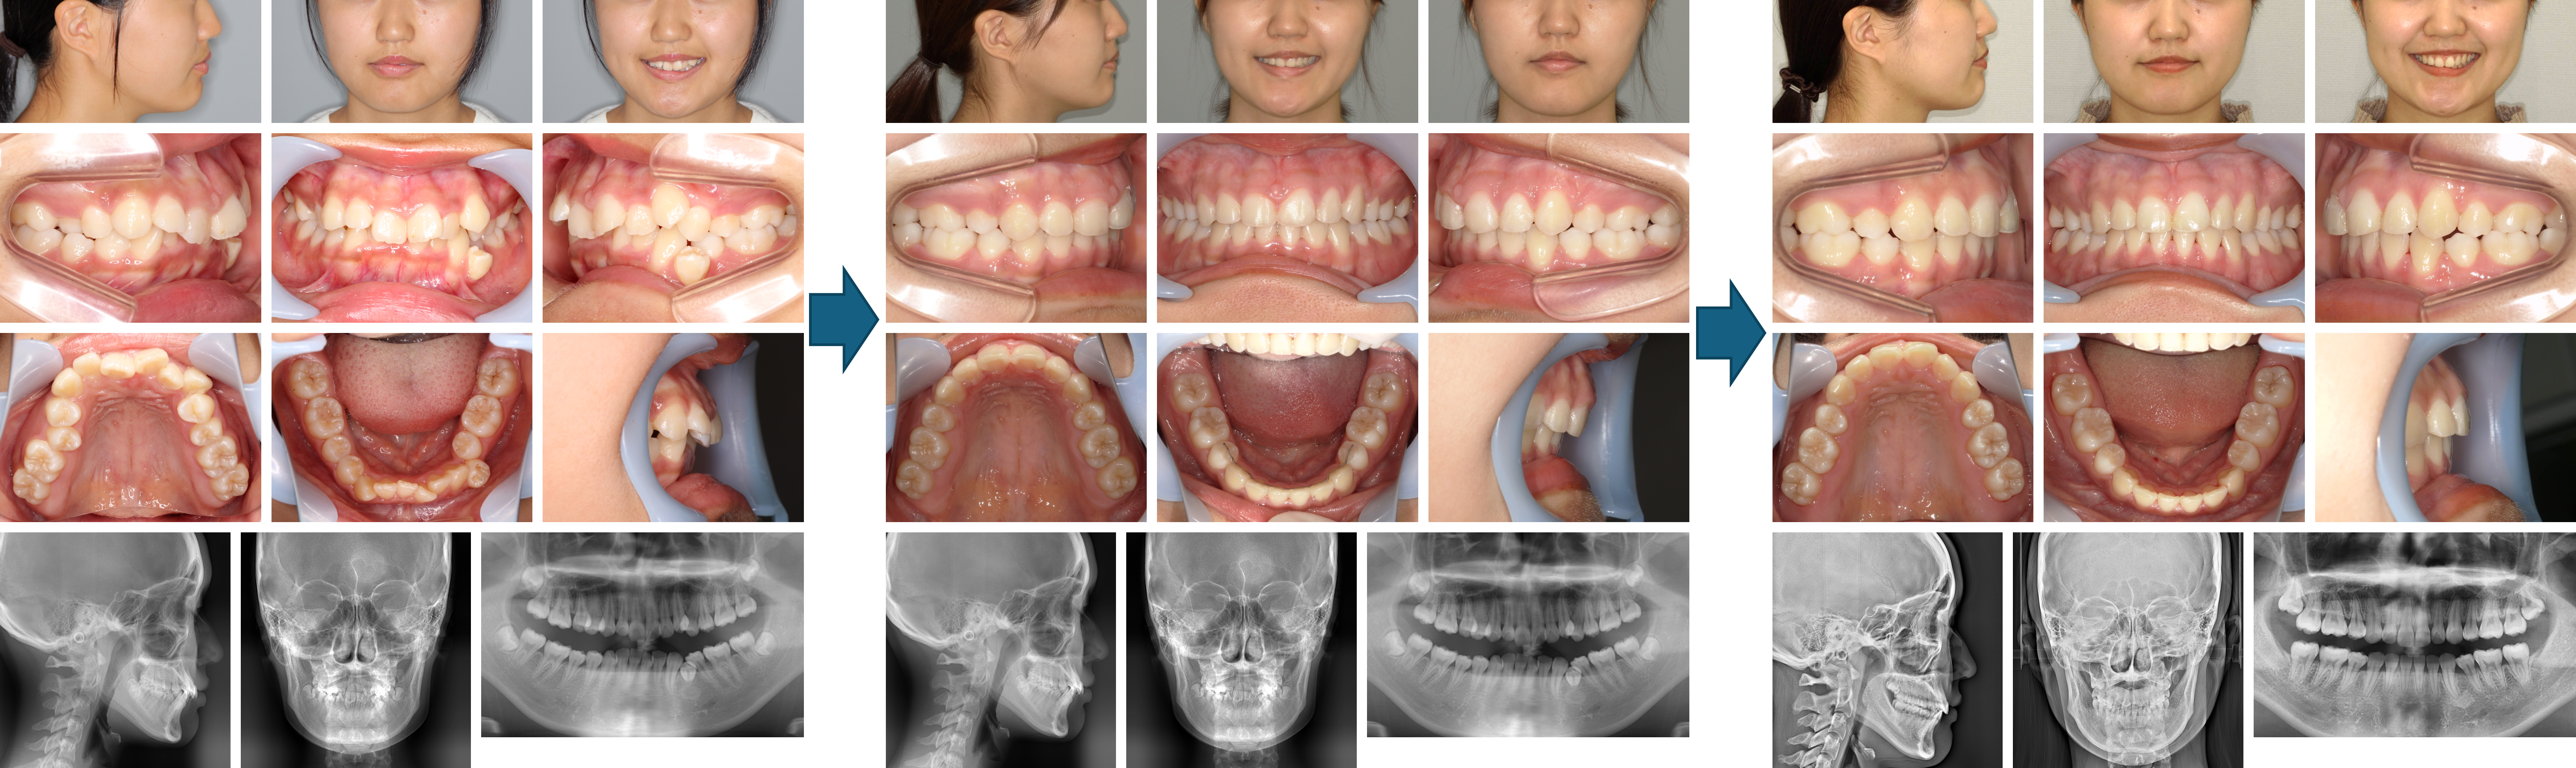

【治療例 K5117】初診時年齢:11歳0か月 / 性別:女性 / 主訴:受け口を治したい

症例の概要:上顎の劣成長および下顎の過成長が認められた骨格性の下顎前突でした。上顎にはクワドヘリックス装置および前方牽引装置を用いて歯列の前方拡大及び前方への成長促進を行いました。その結果、小臼歯を抜歯せず、受け口は改善されました。

主訴:受け口を治したい

診断名:上顎歯列の萌出余地が著しく不足した骨格性下顎前突、ローアングル症例

使用した主な装置:マルチブラケット装置、クワドヘリックス装置、上顎前方牽引装置、顎間ゴム

抜歯/非抜歯および抜歯部位:非抜歯

※こちらの症例は2009年9月から2016年3月に行った矯正治療です(2012年10月~は保定期間)

治療期間:6年6か月

治療回数:60回